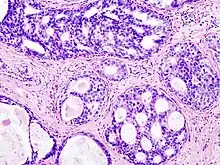

La caractéristique histologique qui distingue principalement le carcinome canalaire in situ de l'invasif est que les cellules tumorales du carcinome canalaire in situ restent confinées au système canalaire-lobulaire mammaire sans envahir le système canalaire-lobulaire mammaire. le parenchyme environnant, la couche myoépithéliale et la membrane basale sont intacts, tandis que les cellules tumorales de l'invasif se sont échappées de la couche myoépithéliale et se sont propagées dans les tissus environnants. Sur la base des caractéristiques moléculaires, certaines études ont classé le carcinome canalaire in situ en quatre sous-types intrinsèques similaires à ceux du cancer canalaire ; ceux-ci incluent les sous-types luminal A, luminal B, le HER2/ERBB2 positifs et le triple négatif. Cependant, il existe une variation dans la prévalence, car le sous-type HER2-positif est plus fréquemment observé dans le carcinome canalaire in situ que dans l'invasif (environ 35 % contre 15 à 20 %, respectivement)[16],[17]. Notamment, différents sous-types intrinsèques de carcinome canalaire in situ ont été associé à des microenvironnements tumoraux et à des voies évolutives distincts par rapport à l'invasif[18].21 Le carcinome canalaire in situ et l'invasif partagent certains facteurs de risque qui contribuent à leur incidence ; ceux-ci incluent l'âge, les antécédents familiaux, la densité mammaire et l'hormonothérapie[19]. Le carcinome canalaire in situ n'est pas considéré comme une maladie potentiellement mortelle et est lié à un taux élevé de survie globale et à une espérance de vie normale[20].23 Après les traitements, le taux de récidive global du carcinome canalaire in situ est d'environ 20 %, dont 50 % sont des récidives in situ tandis qu'un autre 50 % de récidive invasive[21]. Il est donc essentiel d'identifier l'initiation de ces lésions et les relations entre elles.

La théorie traditionnelle supposait que le carcinome canalaire in situ et le carcinome canalaire invasif dérivaient des canaux galactophoriques , tandis que le carcinome lobulaire in situ et le carcinome lobulaire invasif provenaient des lobules[89]. En 1973, les chercheurs montrent que la plupart des carcinomes du sein à un stade précoce, y compris les types canalaires et lobulaires, proviennent de la même structure, à savoir l'unité ducto-lobulaire[90],[91]. La structure canalaire de l'unité ducto-lobulaire se compose de deux couches de cellules, à savoir la couche de cellules épithéliales dans la lumière et la couche de cellules myoépithéliales (entourée par la membrane basale). D'un point de vue morphologique, certains carcinomes canalaires in situ peuvent être visuellement distingués des carcinomes canalaires invasifs à l'étude microscopique, qui se caractérisent par une prolifération néoplasique au sein de l'unité lobulaire du canal terminal et un enrobage invariable par la membrane basale[92], tandis que de petits carcinome canalaire in situ doivent être différenciés des carcinome canalaires invasifs précoces par une combinaison de marqueurs myoépithéliaux ( cytokératine 5/6, la protéine tumorale p63 , la calponine, l'actine des muscles lisses α , etc)[93],[94],[95]. À ce jour, de nombreuses études ont exploré les événements génomiques des carcinomes canalaires in situ et en les comparant avec ceux des carcinomes canalaires invasifs, ils ont mis en lumière les distinctions entre carcinome canalaire in situ et carcinome canalaire invasif synchrones, carcinome canalaire in situ pur et carcinome canalaire in situ avec carcinome canalaire invasif synchrone, et carcinome canalaire in situ primaire et carcinome canalaire in situ ou carcinome canalaire invasif récurrents.